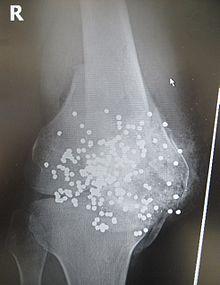

Radiograph of a close-range shotgun blast injury to the knee. Birdshot pellets are visible within and around the shattered patella, distal femur and proximal tibia.

Radiograph of a close-range shotgun blast injury to the knee. Birdshot pellets are visible within and around the shattered patella, distal femur, and proximal tibia